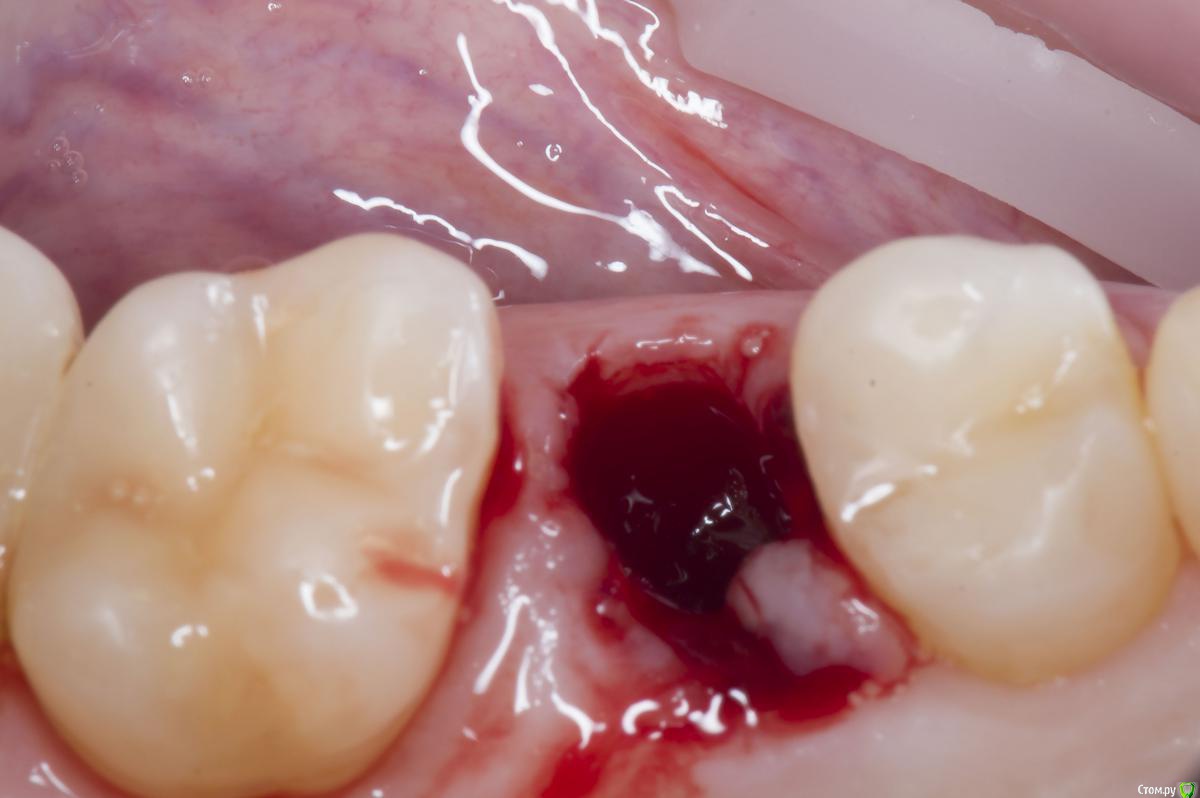

Sampson Опубликовано 10 августа, 2018 Поделиться Опубликовано 10 августа, 2018 (изменено) Очень мило для первого раза.. Здравствуйте коллеги.Сегодня поставил первый свой одномоментныйИзначальная картинаУдалениеСверление и контрольГрафтБолтКТФдмP.S. еще сдт взял с неба и вестибулярно подшил. А с неба заложил prf. Изменено 10 августа, 2018 пользователем Sampson 7 Ссылка на комментарий